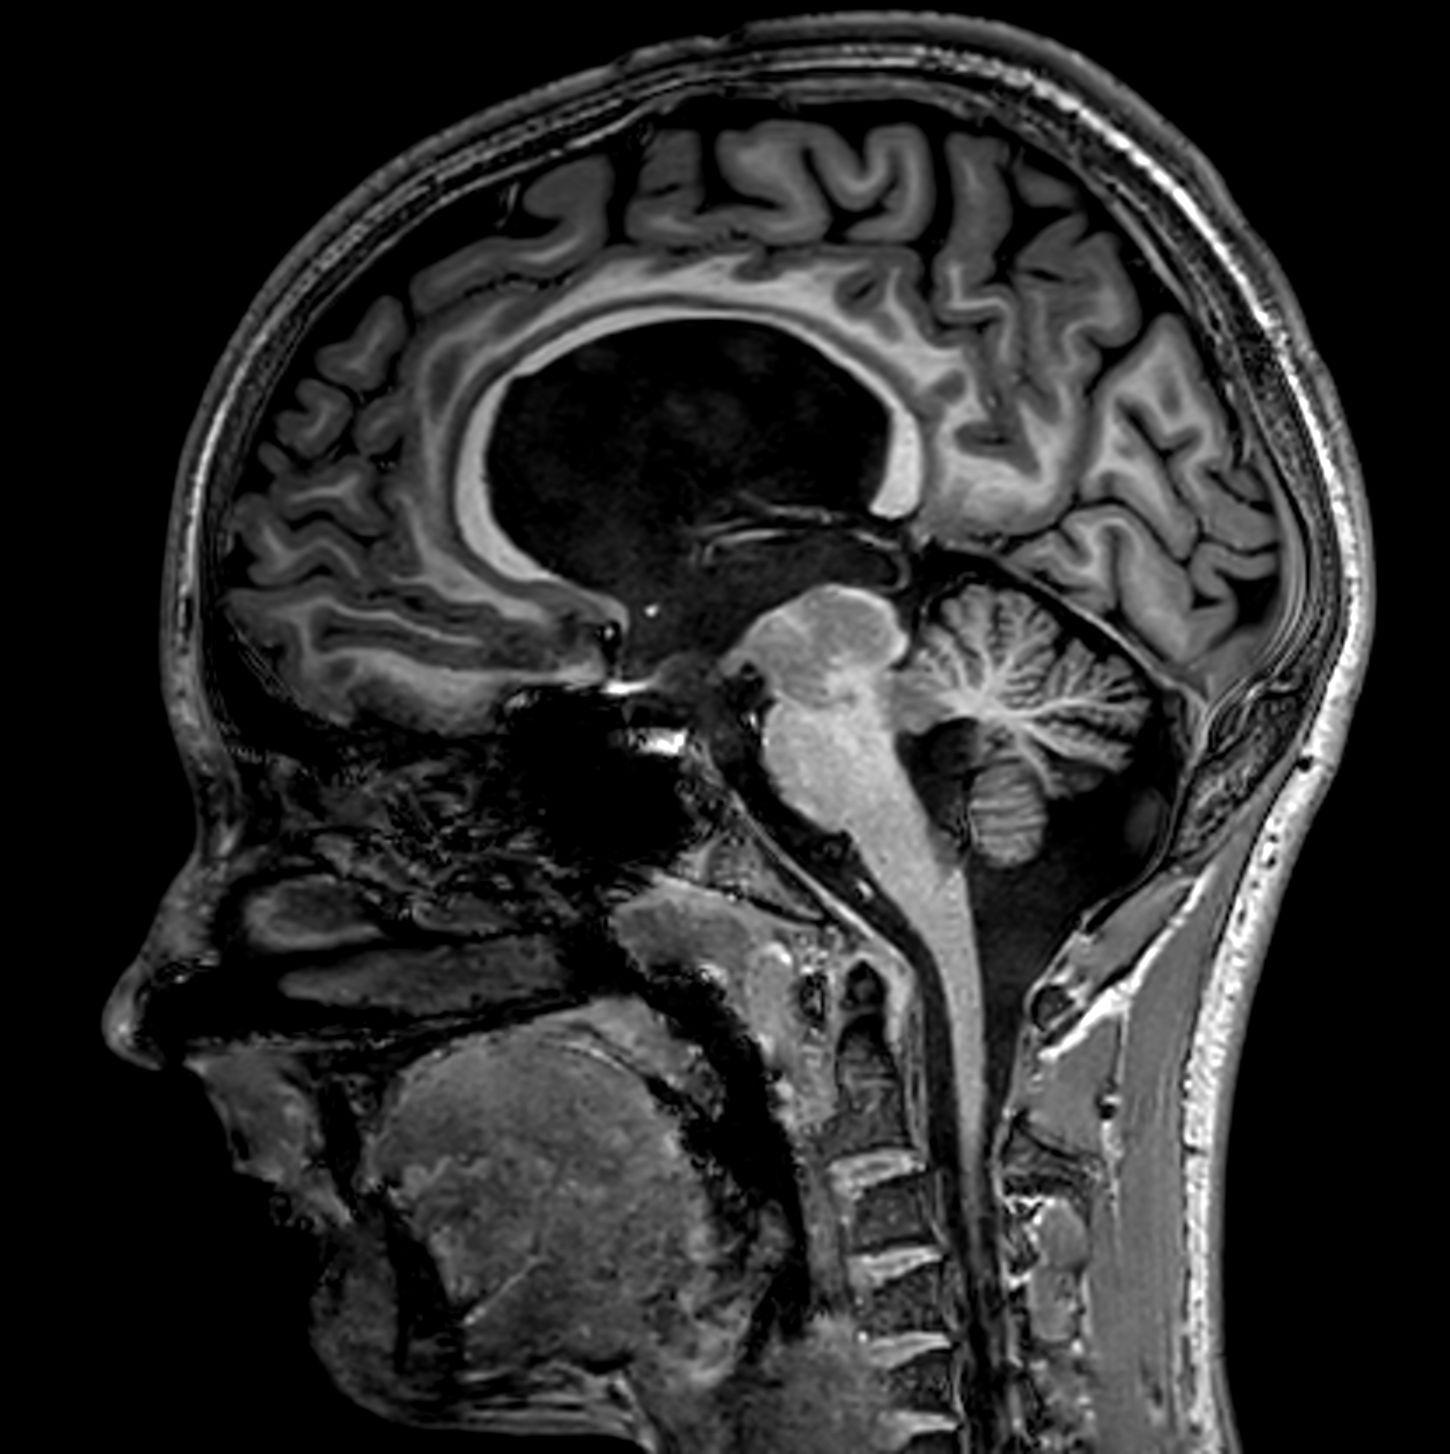

Sagittal 3D bFFE XD